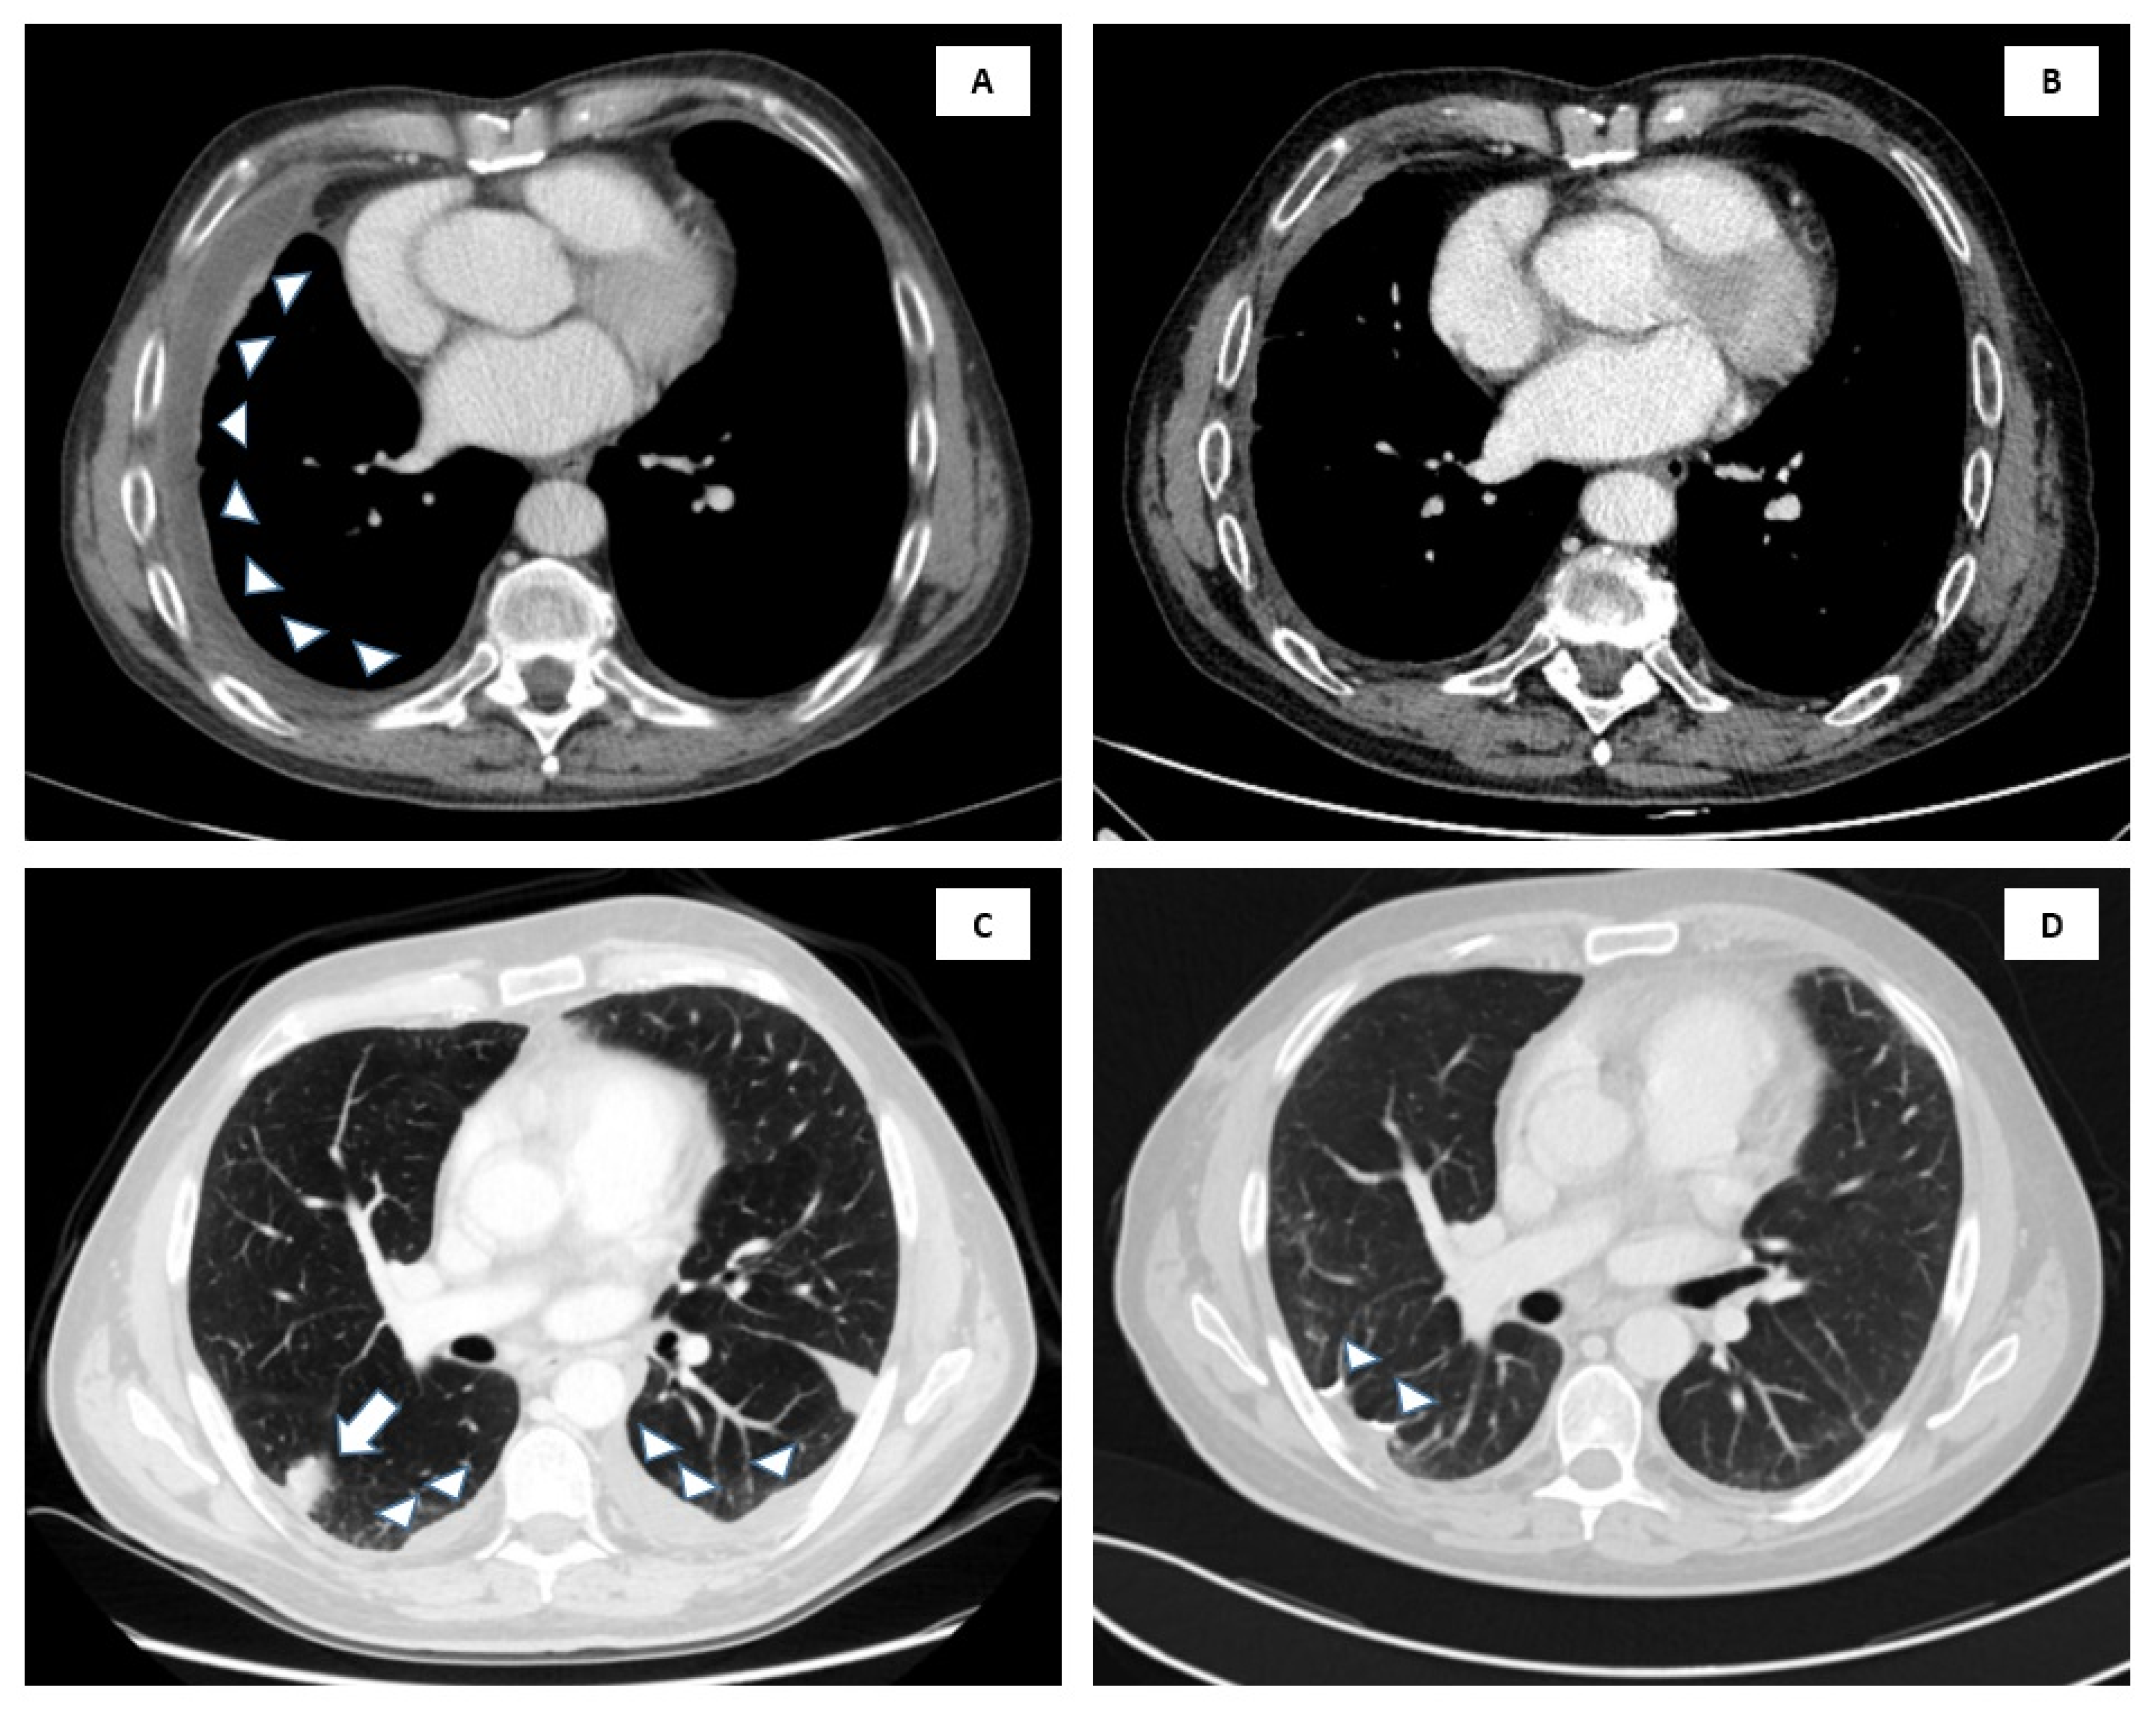

Figure 2.

CT scans of the two cases at onset of large B cell effusion-based lymphoma (EBL) and at the last evaluation. In case 1 at onset (A), but after drainage procedure of pleural effusion, the right pleura is thickened with minimal pleural effusion (arrowheads). At the last evaluation (B), the right pleural thickening and pleural effusion are markedly reduced. In case 2, onset scans (C) show bilateral pleural effusion (arrowheads), at the right upper lobe nodule (arrow). At evaluation post-intervention (D), note the subpleural suture in the site of wedge resection (arrowheads), and the absence of pleural effusion.

After two months of bosutinib, the patient developed severe liver toxicity (G3) that imposed dose reduction. After six months of half-dose bosutinib, the patient had severe pleural effusion recurrence which resolved after bosutinib withdrawal, diuretic, and steroid treatment. Pleural effusion cytologic evaluation was performed and showed no evidence for lymphoma. Immediately after, CML morphological relapse occurred. Mutational analysis showed an absence of compound mutations, and ponatinib was started, obtaining morphologic and cytogenetic remission after three months then DMR at six months. The 16-month follow up CT scan shows a stable minimal thickening of the right pleura, without pleural effusion and any related symptoms, consistent with persistent complete remission (CR) (Figure 2).